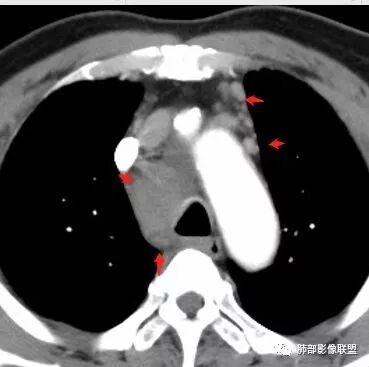

南边:但是我们看纵隔就多发的肿大淋巴结,部分融合成团。

南边:而且这些淋巴结,有些直接主要是压迫支气管壁,但是有些是突入到支气管腔内的。可惜我截的图发不上来。就左上舌段,支气管壁明显的增厚。有些明显腔内突的一个结节的,但是远的没有阻塞的特点。南边:增强以后呢,这个病灶明显强化,部分的似乎有环形强化的迹象,但不是很典型。

我们看这个主支气管的层面,主支气管明显受压,有变形的,但是软骨是没有突破的。